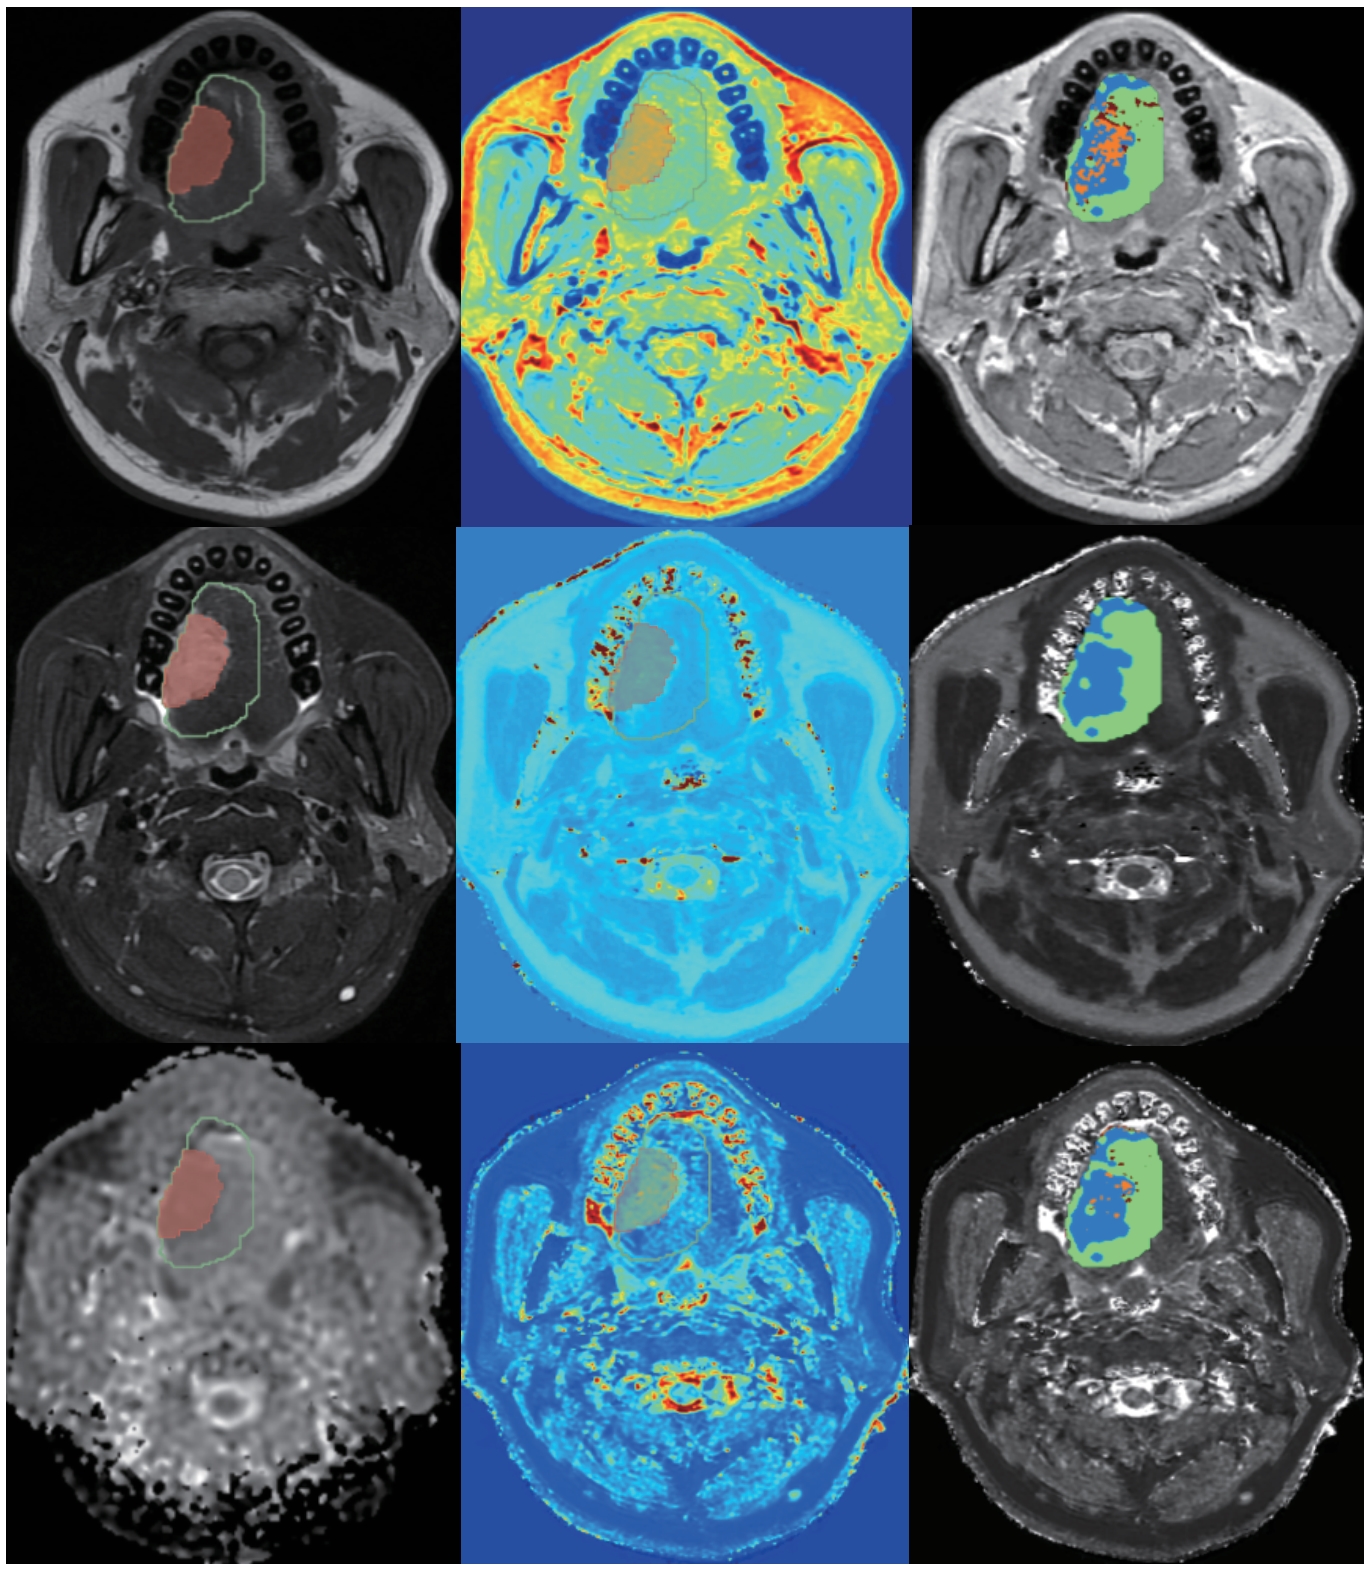

目的·探究合成磁共振成像(synthetic magnetic resonance imaging,SyMRI)技术在口腔癌患者颈部淋巴结转移诊断中的价值。方法·对上海交通大学医学院附属第九人民医院于2023年11月—2024年4月期间收治的、经病理确诊为口腔癌且明确淋巴结转移状况的患者,进行回顾性分析。收集这些患者的术前颌面部磁共振图像,从SyMRI生成的定量图[包括合成T1 map、T2 map及质子密度(proton density,PD)map]、表观弥散系数(apparent diffusion coefficient,ADC)图以及对比增强图像的感兴趣体积区域(volume of interest,VOI)中,提取并筛选直方图特征。通过比较不同瘤周区域的直方图参数,确定最佳范围。在此基础上,进一步结合定量图与ADC图开展生境分析,提取肿瘤侵袭性亚区的生境特征,从而构建预测模型。运用受试者工作特征曲线(receiver operator characteristic curve,ROC曲线)、净重新分类指数(net reclassification improvement,NRI)、综合判别改善指数(integrated discrimination improvement,IDI)以及决策曲线分析(decision curve analysis,DCA),对模型性能进行综合评估。结果·研究共纳入61例口腔癌患者。基于SyMRI提取的瘤内直方图特征对于颈部淋巴结转移的预测曲线下面积(area under the curve,AUC)值为0.798(95%CI 0.673~0.924)。结合ADC图可提高AUC值到0.818(95%CI 0.635~0.861)。通过结合瘤周12 mm的直方图特征和生境特征,预测淋巴结转移的AUC值可进一步提升至0.907(95%CI 0.812~0.993)。NRI、IDI和DCA的分析结果均显示,该模型的预测性能优于临床诊断。结论·基于SyMRI,结合瘤内与瘤周的直方图特征以及生境特征,在口腔癌淋巴结转移预测中展现出较高性能,为无造影剂条件下短时间内成像预测转移淋巴结提供了可行途径。